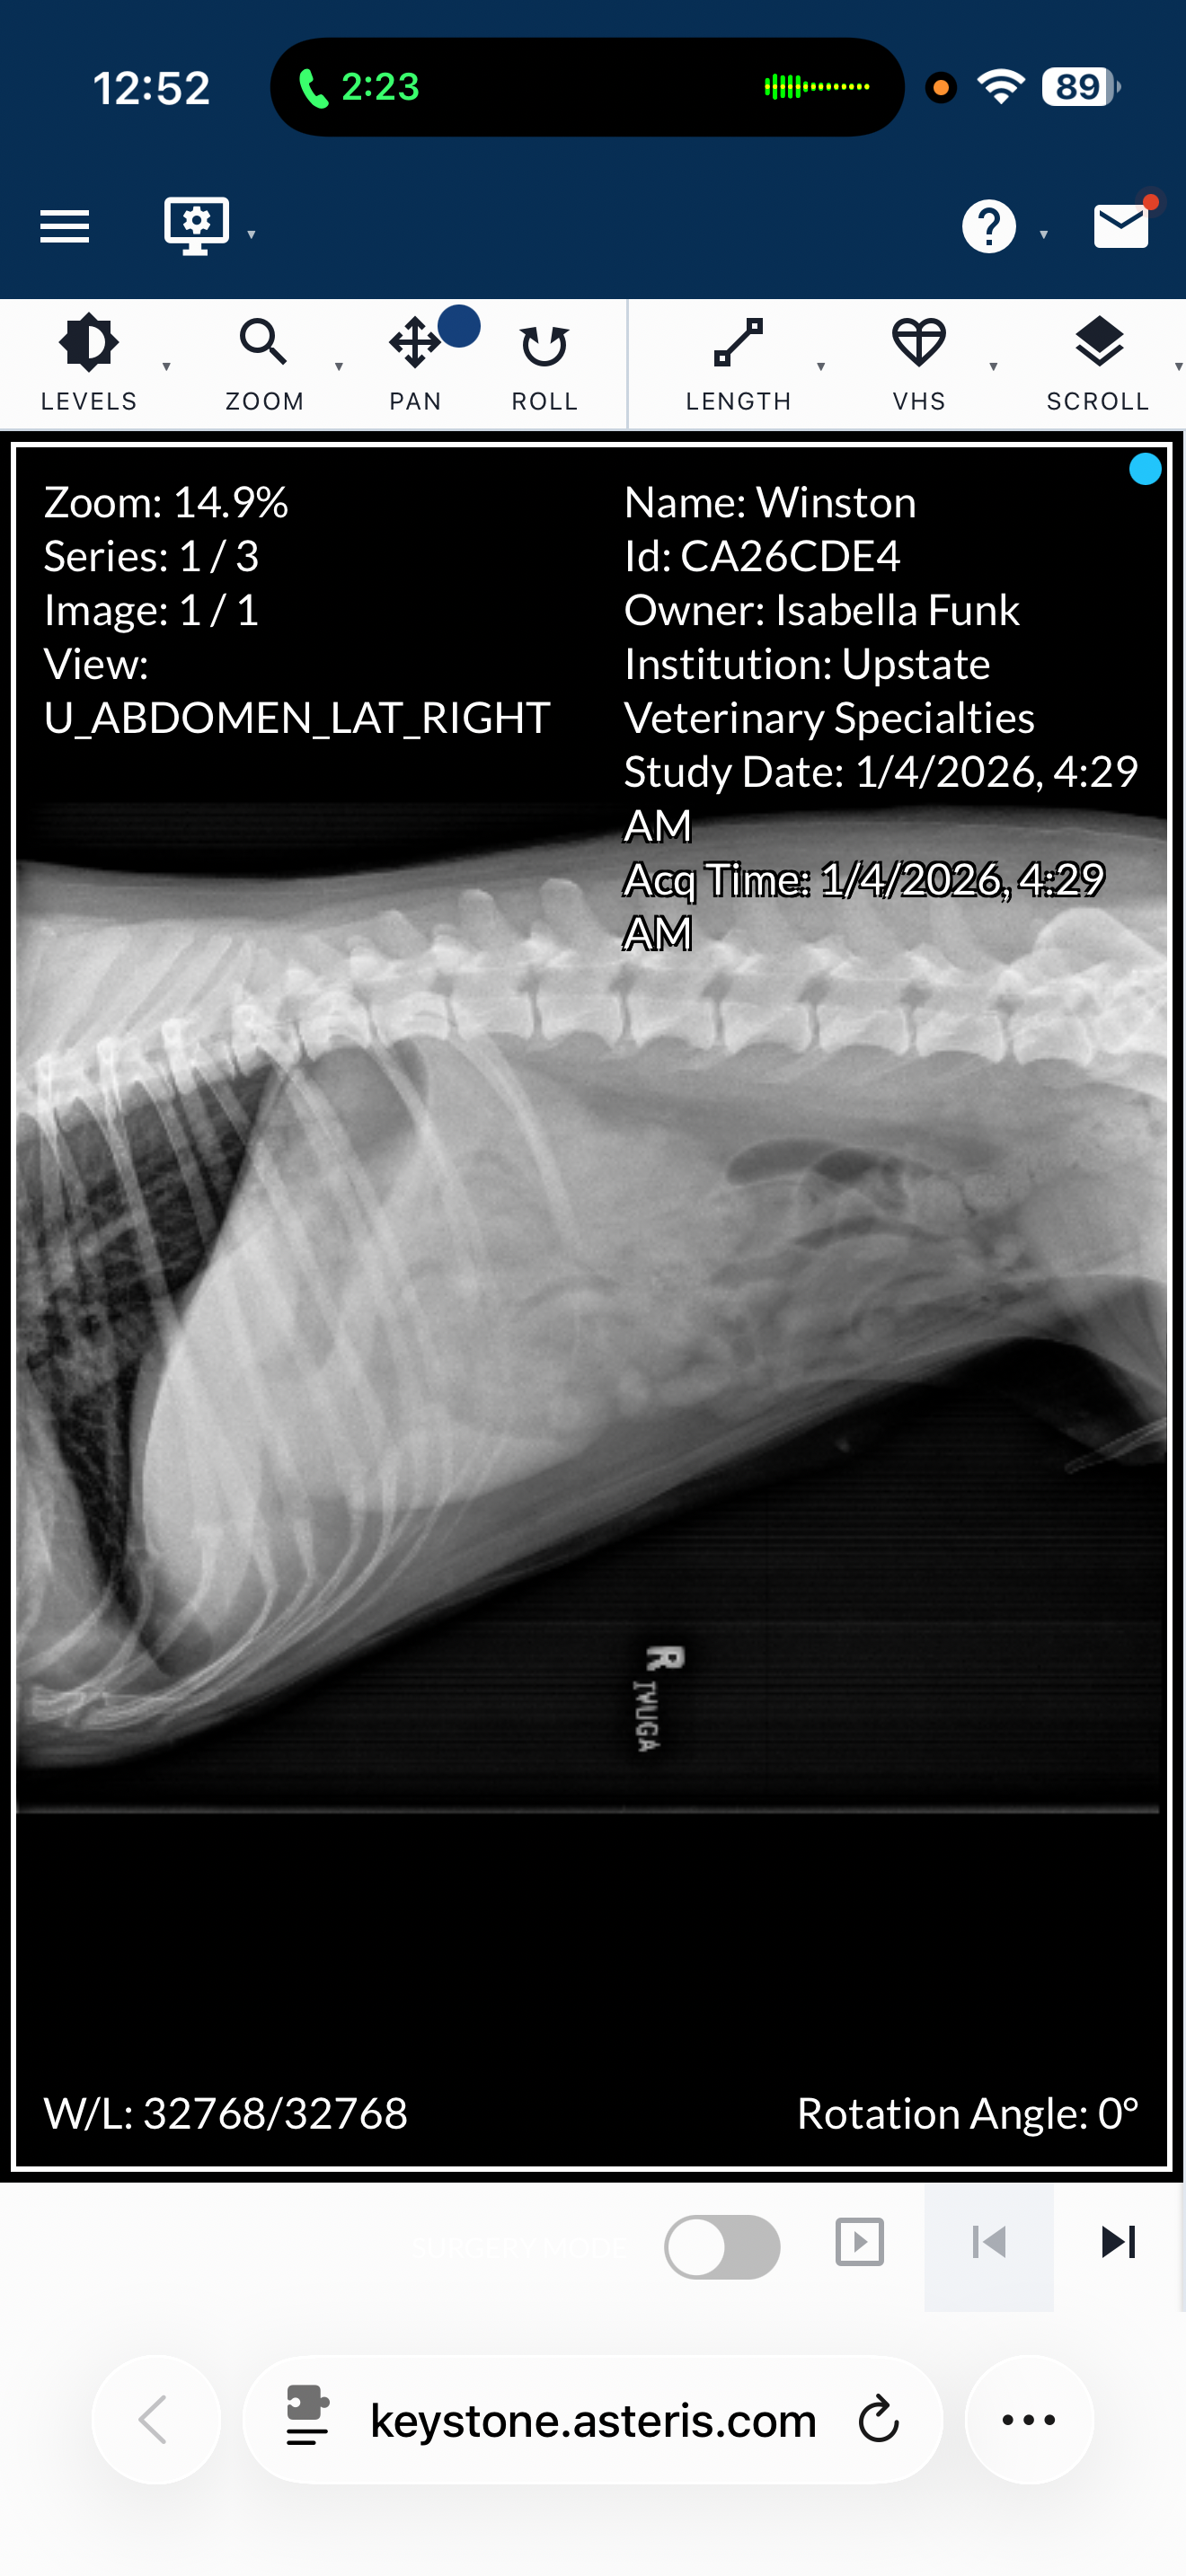

on January 3, 2026 I came home from work to find that my dog was very sick. Winston had obviously puked multiple times while I was away at work and continued aggressively vomiting until roughly 12 AM on January 4th. at that time he began convulsing and showing lots of signs of discomfort, so I decided to take him to the only open emergency vet, Upstate Veterinary Specialty.

At that time, I began applying for CareCredit scratch pay, and all pet card. The only one to approve me was all pet card for $2700. The doctor decided they wanted to hold him for observation. during this stay they would run blood tests, do a chest x-ray and abdominal x-ray to check for any tumors or other issues. All of this came out too roughly $3000. I told them to do what they could with the $2700 that I had.

Blood work came back really good, but the abdominal x-ray did show two blockages in his abdominal region and intestinal pathway. From that knowledge, they decided they needed to keep him longer and do an ultrasound Monday morning January 5th.

This afternoon, Monday, January 5th we went to his primary vet and got more x-rays and the ultrasound done. The results showed no signs of tumors or anything resembling cancer. They also showed that the blockage in his lower intestine was no longer visible the only area they were unable to see was his stomach outflow region. Unfortunately, that area was very sensitive for Winston and they were unable to clearly see what could be going on there.